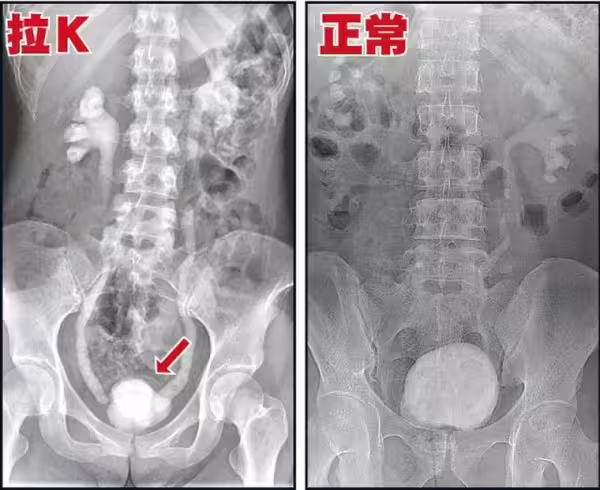

高醫泌尿部主治醫師錢祖明強調,

K他命對膀胱黏膜的傷害是不可逆、

無法恢復的,「醫界能做的很有限」。

其實吸食K他命長久的人,必然會有這種尿頻、尿急、尿痛的症狀,

這是由於K他命的獨特性,持續傷害人體的泌尿系統,導致的嚴重後果。